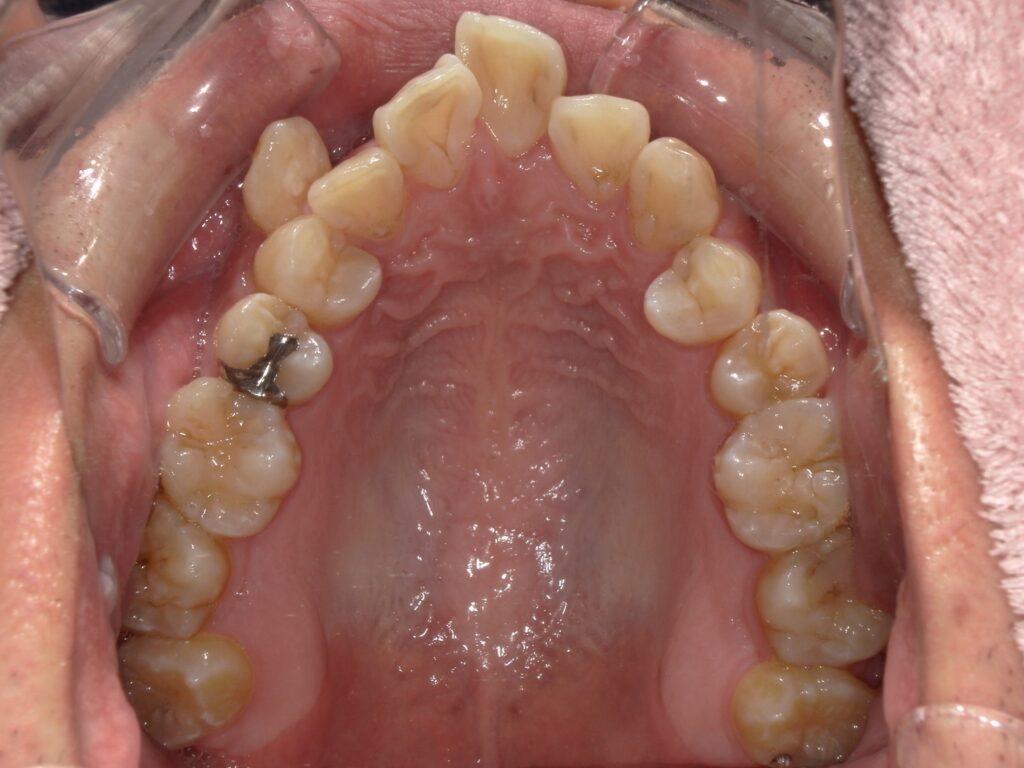

Before

After

ガタつき / かみ合わせ

- 30代男性

- 主訴:前歯のガタつきと噛み合わせを良くしたい

- 矯正方法:インビザラインの非抜歯矯正

- 治療期間:9ヶ月

- 治療費:710,000円

- その他ご要望:治療期間を早くしたい、マウスピースを早く受け取りたい。

- 詳しくはこちら

ご相談内容 前歯のガタつきと噛み合わせが気になると30代男性からのご相談 現状と治療方針 前歯のガタつきが見られます。また、下の前歯を上の前歯が大きく被さっているため、下の前歯が見えない過蓋咬合(ディープバイト)が見られます。奥歯をさらに後ろに下げる遠心移動と、歯と歯の間にわずかなスペースを作る方法で矯正を行いました。 治療結果 ガタつきと噛み合わせを9ヶ月で改善できました。 振り返り 今回の患者様は他院で不信感があり、ご紹介という形でセカンドピニオンを受けるために当院にお越しいただきました。お仕事が多忙のため治療期間を早くすることが一番重要なご要望でしたが、全体矯正にも関わらず9ヶ月で矯正を終えることができたことに大変喜んでいただけました。 リスク・副作用 マウスピースの装着時間を守っていただけないと矯正治療に時間がかかり、場合によっては治療がうまく進まない可能性があります。